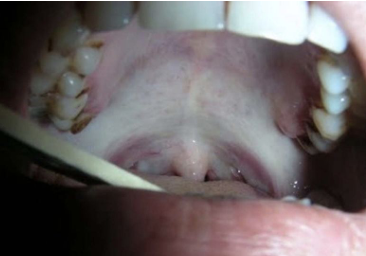

oral submucous fibrosis

-premalignant condition seen in 1-2% of areca nut and betel quid users- India, southeast Asia, Taiwan, NYC

-mucosa may appear white due to underlying fibrosis

-sometimes changes “better felt than seen”- “piano wire” feel

-patients report burning and increasing trismus

-progressive scarring/fibrosis limits mouth opening

-dysplasia may develop in long-standing lesions (7-13% of pts develop SCC)

oral submucous fibrosis clinical features

-mucosa develops blotchy, marble-like pallor and progressive stiffness of submucosal tissue

-most commonly affects buccal mucosa, retromolar area, soft palate

-palpable submucosal fibrous bands on the buccal mucosa, soft palate, labial mucosa

-extends to involve oropharynx, upper esophagus

-if tongue involved: becomes immobile, diminish in size, devoid of papillae

-white patch often noted- reflect epithelial change (most are hyperkeratosis, 10-15% epithelial dysplasia, 6% SCC)